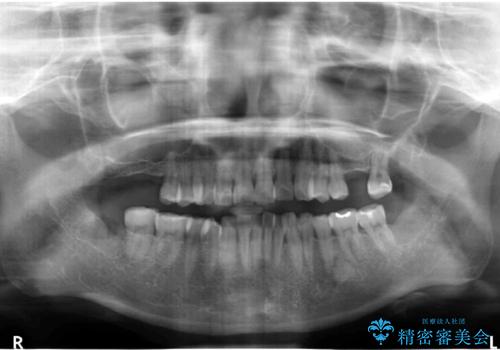

- 前歯のがたつきを主訴に来院。

奥歯も少なく、左上奥歯はブリッジにすることになりました。

左下の前歯を中に入れるスペースを確保する目的で左下の奥歯を後ろ移動させました。

また、左下の小臼歯の捻転はマウスピースで治りにくいため、

事前にワイヤーによる部分矯正を行い、矯正用ミニスクリューを植立しています。

右上大臼歯2本の欠損については、インプラント治療をお勧めしましたが、ご希望によりそのままとなりました。